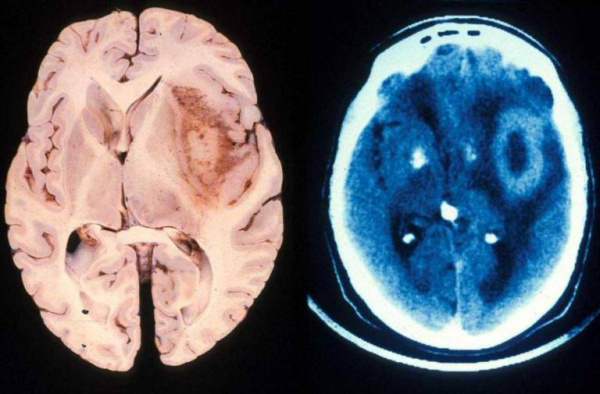

- Компьютерная томография. Выявляет изоденсное церебральное образование с гиподенсным участком центрального некроза, перифокальным отеком, геморрагическим компонентом. Характерен масс-эффект. КТ с контрастированием демонстрирует кольцевое неравномерное окрашивание. Микроскопическая инфильтрация обычно распространяется за пределы визуализируемого очага.

- Магнитно-резонансная томография. МРТ с контрастом гадолиния показывает образование неправильной формы с плотным кольцом усиления, некротизированным центром. Некроз считается отличительной чертой глиобластомы. Также могут визуализироваться окружающий образование вазогенный отек, кровоизлияния, кистозный компонент, искривление или смещение желудочков. Примерно в 13% случаев наблюдается многоочаговость поражения.